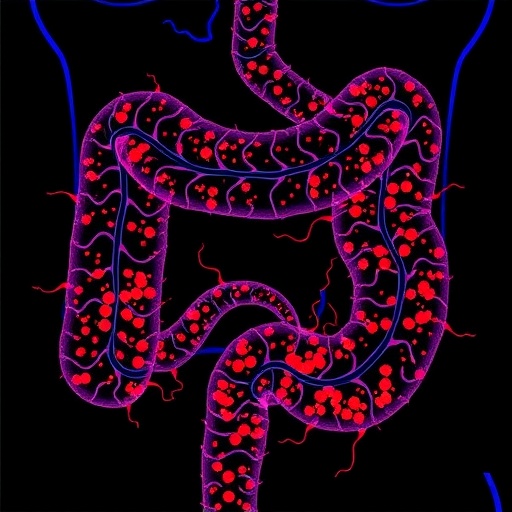

usp7:-key-immunotherapeutic-target-in-colorectal-cancer

USP7: Key Immunotherapeutic Target in Colorectal Cancer

January 25, 2026

In a groundbreaking study poised to reshape our understanding of colorectal cancer and its interaction with the immune system, researchers…

Read More